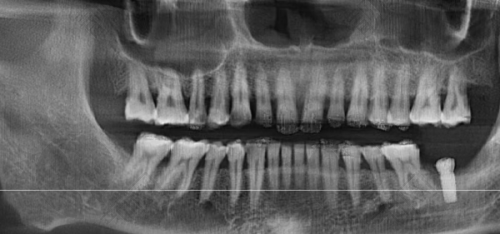

上海鼎植刘正欢种植牙实例

曾有一位患者,由于长期牙齿缺失,导致牙槽骨重度萎缩,普通的种植牙技术难以实施。刘正欢院长经过详细的检查和分析,决定为患者采用穿颧种植技术。在手术过程中,刘院长凭借不错的技艺和丰富的经验,精细操作,成功为患者植入种植体。术后,患者修复良好,牙齿功能和美观度都得到了极大的改善,对刘院长的医术赞不绝口。